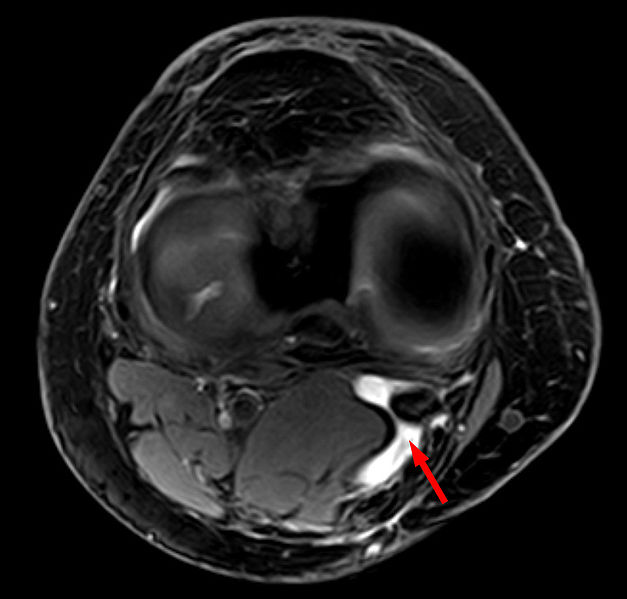

Picture 1: Bakers Cyst

In severe cases, Baker’s cyst can rupture and become complicated because of the protrusion of fluid down the leg between the muscles of the calf. In cases like ruptured Baker’s cyst and other severe cases, a Baker’s cyst surgery is important. A Baker’s cyst surgery like removing or repairing the torn cartilage will be of great help to address the problem. In some conditions, if despites of different treatments and therapies, the overproduction of fluids recur, the Baker’s cyst will be removed through a surgical procedure. However, a patient should undergo several pre-operating procedures before a surgical operation be facilitated. These procedures should include physical examination. A medical history is also important to track the records of a patient to avoid further complications eventually. A join x-ray will also be of help to show the presence of arthritis in the knee joint. Transillumination and Magnetic Resonance Imaging or MRI as well as Ultrasound are also important to evaluate the patient’s knee joint’s condition.